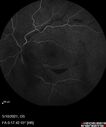

Elevated Episcleral Venous Pressure and Retinal Hemorrhages in both eyes293 views78 year old female with chronic red eye. The eyes are red all the time now. She is on Xeralto because of a history of blood clots in her lungs (2005 about). She has not had problems since. She has had floaters for many years. Ever since her eyes got funny she sees more floaters in both eyes. She had a brain scan over 6 months ago which was OK. She also had double vision when this first started which went away. She could not drive for a few months.

VA OD: Dcc20/32-1

VA OS: Dcc20/125

IOP: TP: OD:17 OS:16

Neuroimaging did not show a CC fistulaJul 13, 2021